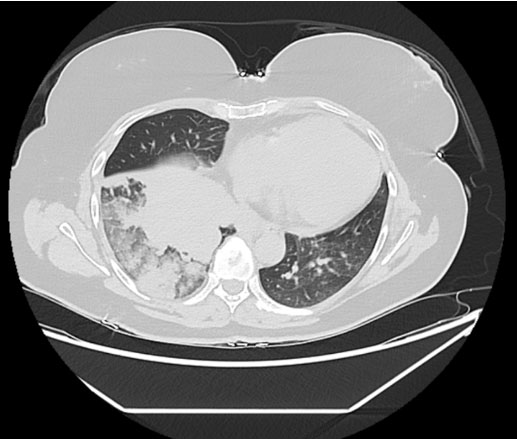

On admission, her laboratory results showed: elevated calcium (4.8 mmol/L), acute kidney injury (urea 17.3 and creatinine 176), a raised alkaline phosphatase (ALP) (168) with normal vitamin D (56) and PTH (1 pmol/L—appropriately suppressed). An electrocardiogram (ECG) showed normal sinus rhythm with left axis deviation, and an admission chest X-ray showed a large area of opacification in the right lung base. She was treated with intravenous fluids and received a first dose of zoledronic acid (4 mg intravenous). She underwent a computed tomography scan of her chest, abdomen and pelvis which showed a large right-sided pulmonary mass with maximum dimension of 8 cm, significant mediastinal lymphadenopathy and narrowing of the right main and lower lobe bronchus, and multiple bony metastases (Figure 1 and Figure 2). There was sparing of the left lung.

Figure 2: Coronal image of CT thorax, abdomen, and pelvis (282 mA, 120 kV) showing large pulmonary mass with significant lymphadenopathy and mediastinal involvement.